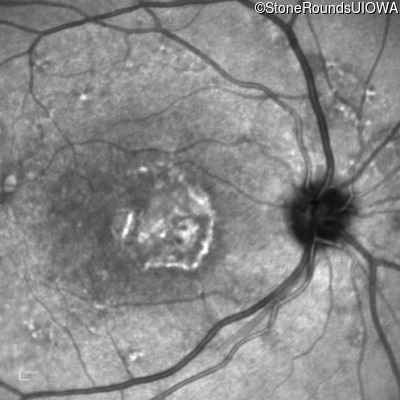

Age at visit: 59 years (Visit 3)

This 59 year old woman first noticed vision loss in her right eye a few months earlier. She has a cousin with Rhodopsin-associated RP.

AR Stargardt Disease ABCA4 Arg219Thr AGA>ACA Gly863Ala (G)GA>(G)CA AR